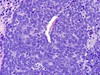

What type of EB is this?

On electron microscopy, what cytological structures would be absent in the specimen?

What gene mutation is present?

Recessive dystrophic EB (RDEB)

Absence of anchoring fibrils

- Compound heterozygous mutation within the COL7A1 gene, leading to a truncated collagen VII protein that in most cases is nonfunctional